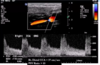

Patient has Lt ICA 100% occlusion. Rt carotid system shown below. PSV = 208 cm/s in proximal Rt ICA.

Most likely diagnosis?

mild Rt ICA stenosis (<50%)

since Lt ICA is 100% occluded, there should be elevated Rt CCA velocities (CCFA*)

plaque in proximal Rt ICA is <<50% ⇒ elevated velocities across Rt ICA are likely due to CCFA

*CCFA = compensatory carotid flow augmentation